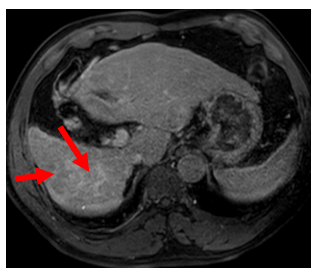

Hình 2: Hình ảnh chụp cắt lớp vi tính ổ bụng tháng 1/2021 (bên trái) và tháng 4/2022 (bên phải): Hình ảnh u gan phải sau điều trị kích thước 18x22 mm, còn tăng sinh mạch (mũi tên đỏ). Hình ảnh u gan phải sau điều trị kích thước 18x22 mm, không còn tăng sinh mạch (mũi tên xanh).